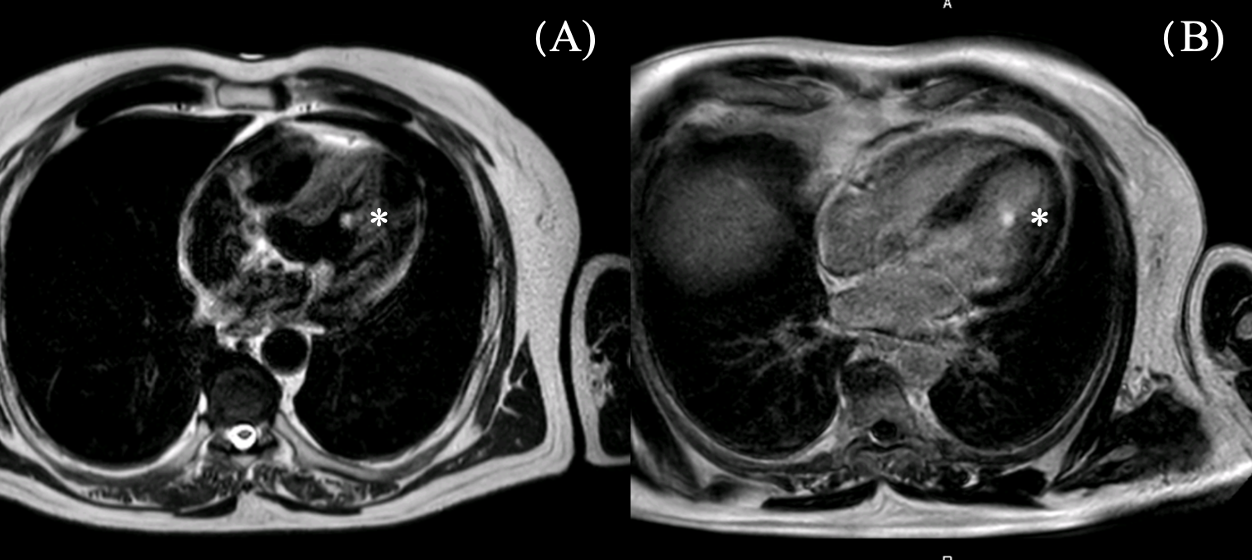

2.1. Diagnostic Assessment